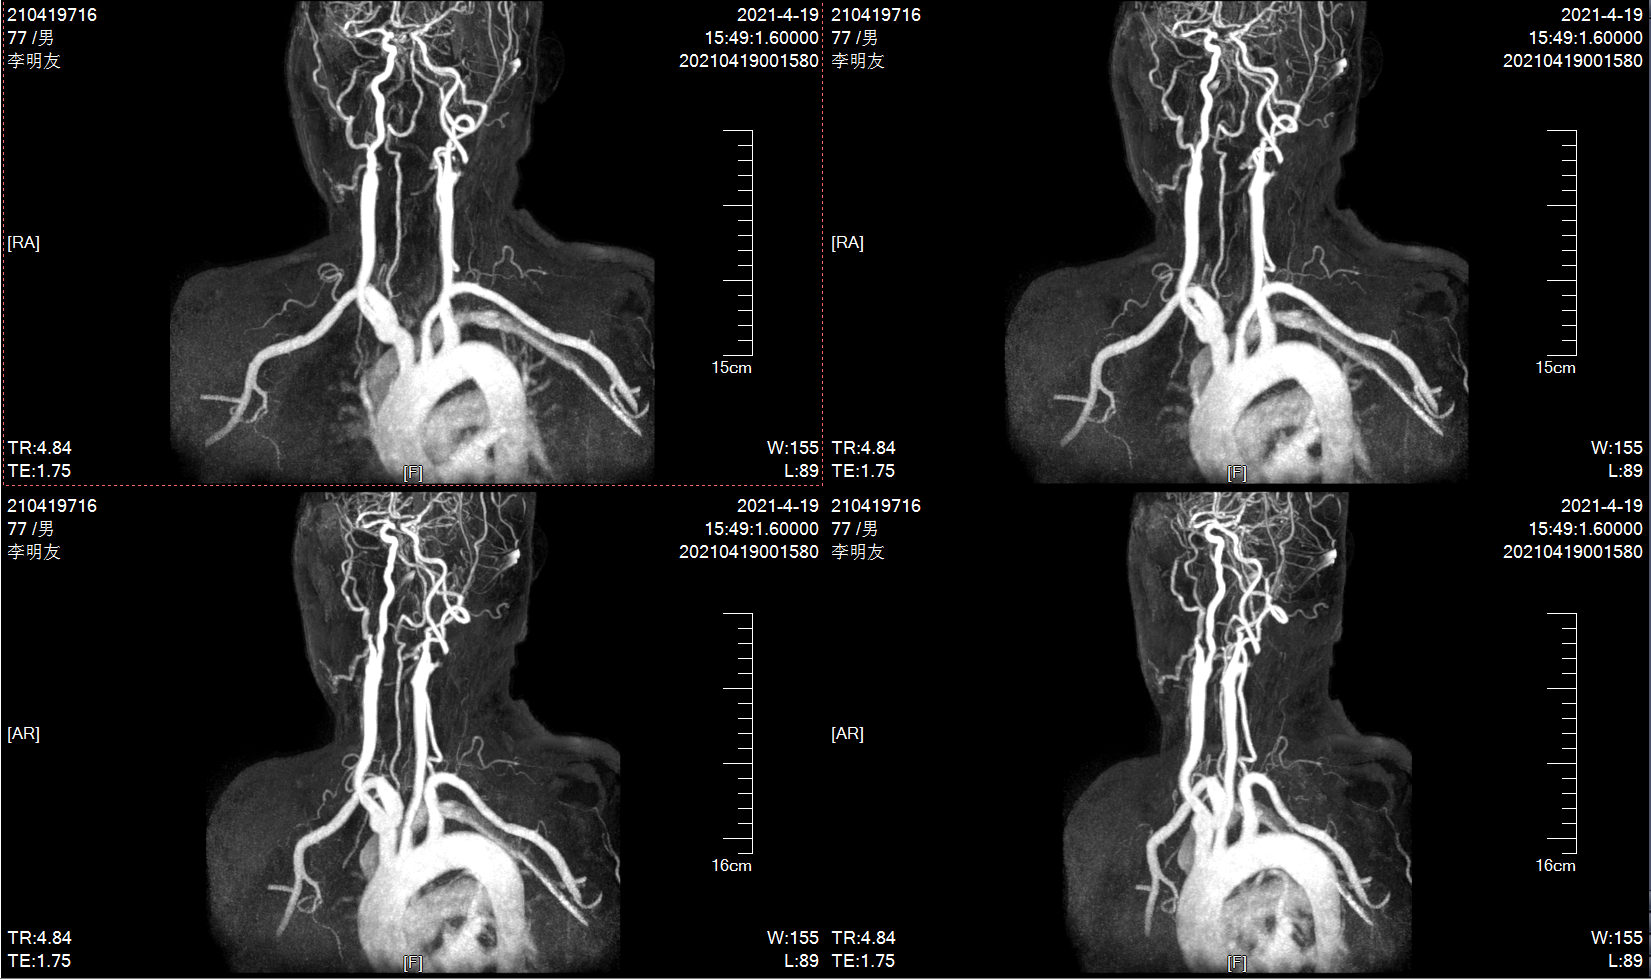

10个月前MRA示左侧颈内动脉轻度狭窄

MRA示左侧颈内动脉重度狭窄